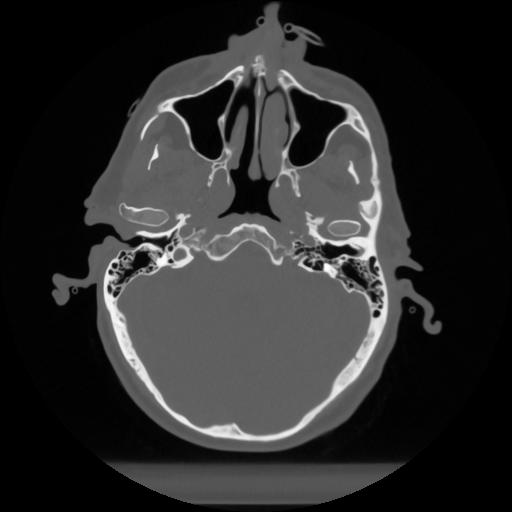

12 P.BLANDAS,,Vol,0.5,P.BLANDAS,,